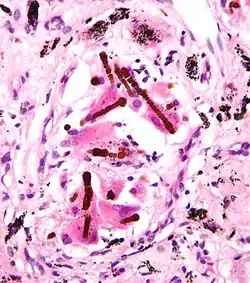

A fiber cannot be identified or ruled out as asbestos, either using the naked eye or by simply looking at a fiber under a regular microscope. The most common methods of identifying asbestos fibers are by using polarized light microscopy (PLM) or transmission electron microscopy (TEM). PLM is less expensive, but TEM is more precise and can be used at lower concentrations of asbestos.

There is experimental evidence that very slim fibers (<60 nm, <0.06 μm in breadth) tangle destructively with chromosomes (being of comparable size).[27][28] This is likely to cause the sort of mitosis disruption expected in cancer.